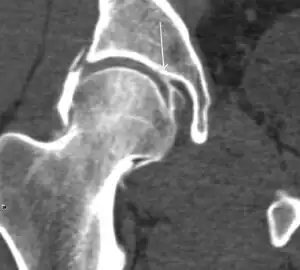

MRI has been shown to have 100% sensitivity and specificity in prospective studies of occult hip fractures. These fractures were diagnosed by bone marrow edema and a low signal fracture line, mainly on T1 or T2 weighted images (Figure 10).[1]

Figure 10:

Stress femoral neck fracture in a young athlete barely visible in X-ray film as a sclerotic line (arrow)[1]

In this case, Tc 99 scintigraphy shows a band of uptake[1]

Furthermore, T1 (left) and DP fat saturated (right) weighted MR images showed the fracture line and a pattern of edema.[1]

Quite often, CT is widely available unlike MRI, especially in the acute setting. CT is performed in this setting when doubt about the existence of a fracture persists following plain radiograph. Modern multidetector computed tomography (MDCT) shows results comparable with MRI for detecting occult fractures.[1]